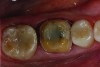

Treatment began on the mandibular lower right quadrant. Teeth Nos. 28, 29, and 31 received new composite fillings. A composite core was placed in tooth No. 30, and the tooth was prepared for a full-contour zirconia crown (Figure 2). The gingiva was retracted to reveal the margin for the digital impression. iTero® (Align Technologies, aligntech.com) was used to scan the operative quadrant, the opposing arch, and finally, the patient’s bite. The resulting digital proposition produced a virtual cast for evaluation of complete capture of data and an accurate rendering.

Figure 2: Crown preparation of tooth No. 30.

Figure 2